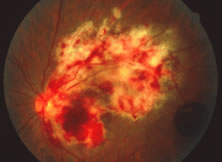

The ARN patient typically presents with progressive visual blurring in one or both eyes occurring over several weeks. These patients often are initially treated with corticosteroids, antitoxoplasmosis drugs, and other medications before arriving at the correct diagnosis. Examination reveals a prominent anterior uveitis that may be granulomatous or nongranulomatous (Fig. 1). Inflammatory signs may be prominent and cause severe pain (Fig. 2). The uveitis may be diffuse and so severe that it causes proptosis. These signs, and the diffuse vitreitis that makes the view of the retina difficult, may contribute to the high degree of delayed and/or misdiagnosis that occurs in the early stages of the disease. Significant vitreous cellular infiltration is seen in the presence of retinitis that is manifest by opacification of the retina, often most prominently in the periphery. Posterior pole involvement may include retinitis, as well as inflammation of the optic nerve head. Optic neuropathy might be the first sign of ARN with subsequent development of other retinal manifestations.8 Ultrasonography and computed tomography (CT) might be helpful in cases of ARN associated with optic nerve edema revealing enlargement of the optic nerve sheath.9 Even in ARN patients who are not immunocompromised and who have no clinical evidence of encephalitis, magnetic resonance imaging of selected cases has shown lesions of the lateral geniculate, optic tracts, and chiasma, which suggests that the virus spreads through the central nervous system (CNS) by axoplasmic transport from the retinal ganglion cells.10 A secondary retinal vasculitis is common, often accompanied by a mild number of retinal hemorrhages. Days to weeks after onset of the infection, the discrete peripheral lesions typically coalesce into a white or yellow ring of infected retina, and the associated vasculature is obliterated (Fig. 3). Necrotic retina desquamates into the vitreous resulting in vitreous sheets.3,6 Eventually, most untreated eyes can be expected to develop retinal detachment resulting from development of multiple full-thickness retinal breaks accompanied by traction or exudation.11 Giant retinal pigment epithelial tears have also been reported.12